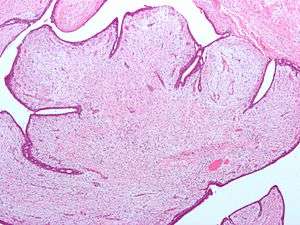

| Fibroepithelial neoplasm (Phyllodes tumor). | |

Fibroepithelial neoplasms (or tumors) are biphasic tumors. This means they consist of epithelial tissue, and stromal or mesenchymal tissue. They may be benign or malignant.[1]